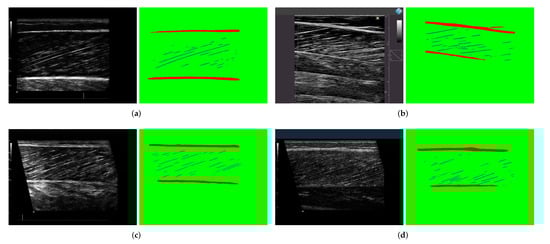

3.4. Post-Processing